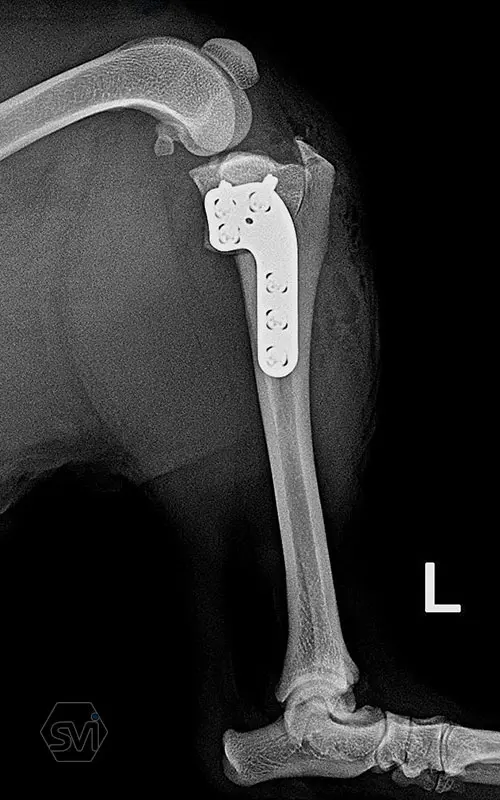

Introducing the precontured polyaxial locking TPLO family, now available in all sizes:

- Mini: 2.0mm (thinner and thicker version)

- Midi: 2.4mm

- Small: 2.7mm

- Standard: 3.5mm (both in short and extended versions)

- Giant: designed for 4.0mm screws.

It has a number of advantageous features that make it stand out from standard TPLO solutions:

- well designed that follows the anatomical position and ideal hole placement

- precontoured, its use shortens the surgical time, no greater physical force is required for bending

- locking system for greater stability

- polyaxial screw insertion, the direction of screw insertion can be freely selected in a 30-degree circle while maintaining angular stability! (this is very useful to avoid driving the screw into the joint, and the temporary fixing can also be avoided with a K-wire)